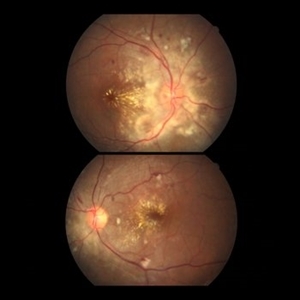

Hypertensive Retinopathy

Jan 8 2022 by Gayathri Mohan

Color fundus image of both eyes showing a resolving hypertensive retinopathy, taken one month post episode of malignant hypertension.

Photographer: Dr Gayathri Mohan

Imaging device: Canon

Condition/keywords: hypertensive retinopathy, malignant hypertension